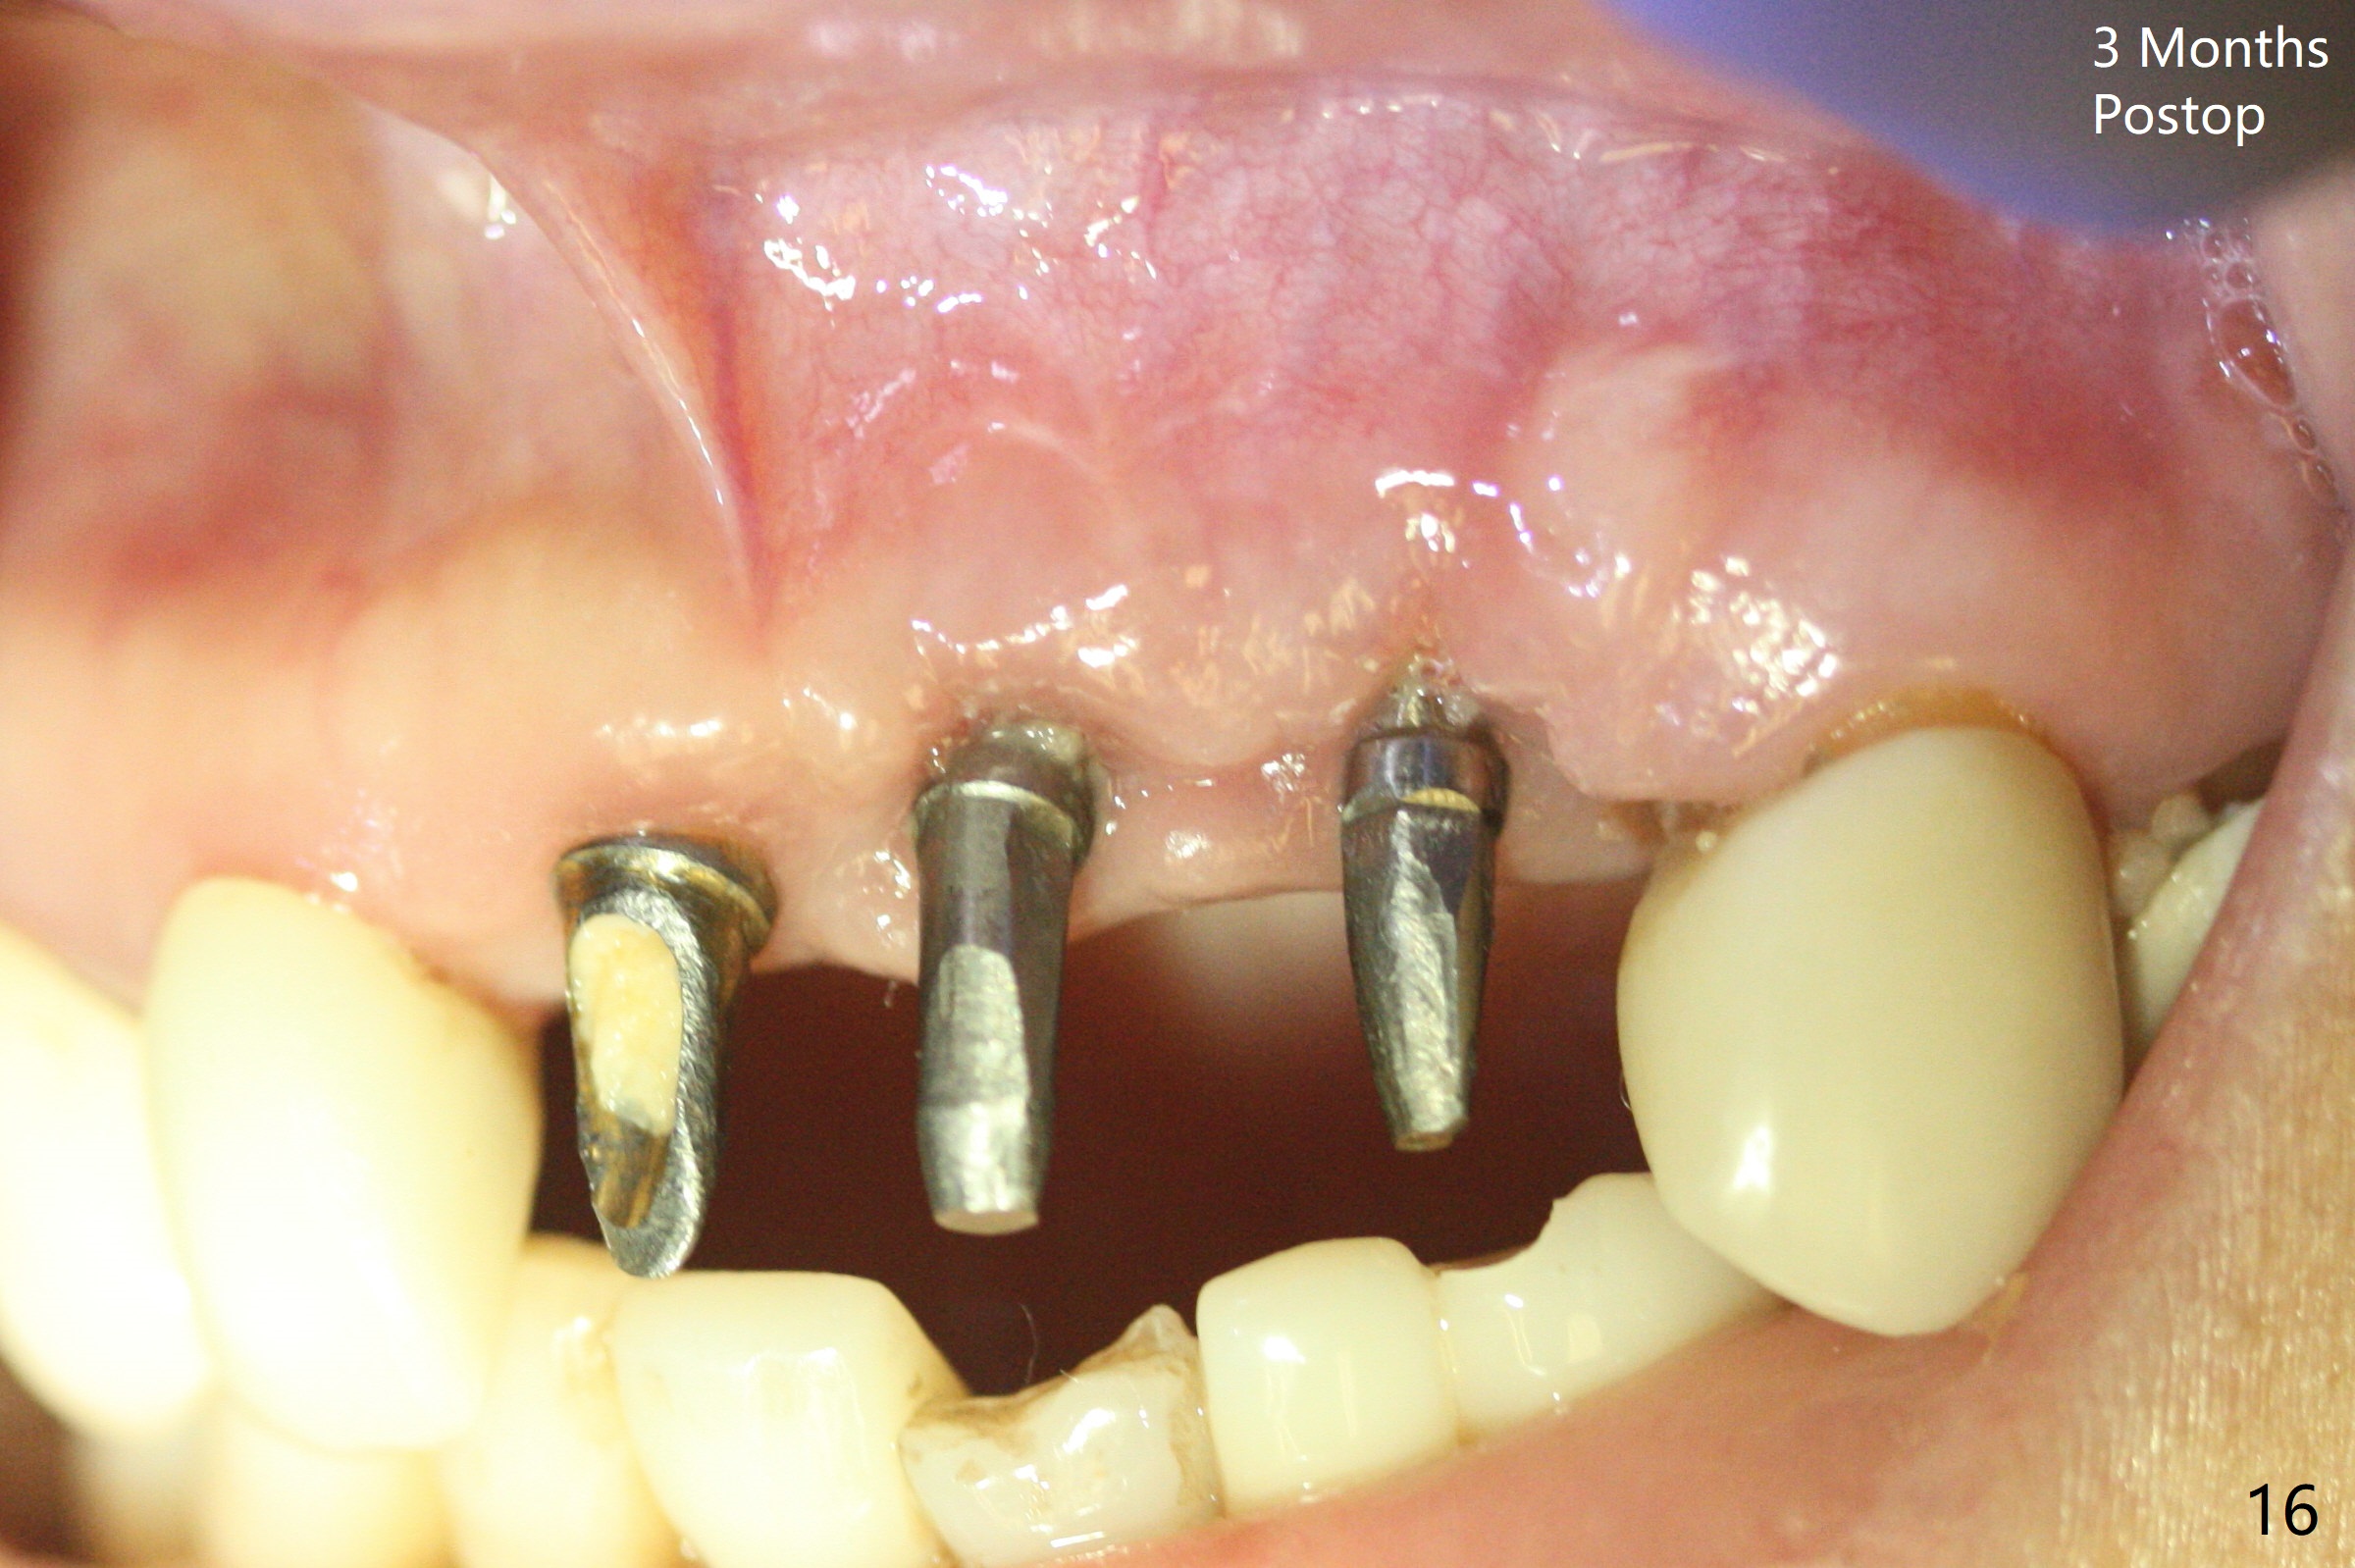

Incision shows exposure of microthreads at #9 and major threads at #10 due to buccal placement (Fig.1). There is bone palatal to the implant at #10 (Fig.2 P), to which a new implant will move. After implant removal, a narrower 1-piece implant (2.5x14(4) mm) is placed palatally at #10 (Fig.3,4) in combination of guide and free hand. At the site of #9 after implant removal, the guide is not used; a 3x17 mm angled 1-piece implant is placed with bad trajectory (Fig.5,6). After re-adjustment (Fig.7), the implant is placed at the right orientation (Fig.8). It appears that the guide is helpful. Allograft is placed mainly buccally (Fig.9,10 *), followed by a piece of collagen membrane (Fig.11). After tension release, flaps are approximated (Fig.12). The buccal gingiva at #9 and 10 recede nearly 2 months postop (Fig.13). Less recession at #9 is associated with more inflammation (Fig.14). The margin of the provisional is adjusted for gingival margin down growth and easy self cleaning with Water Pik (Fig.15). One month later, the gingival inflammation reduces, while there is no obvious buccal collapse (Fig.16,17). Impression is taken after laser gingivectomy nearly 4 months postop (Fig.18). While the gingiva around the implant at #9 is inflamed (periimplantitis?), the gingival cuff at #10 is well formed 5.5 months postop immediately before cementation (Fig.19). The buccal concavity at #10 is minimal (Fig.20). The gingival inflammation at #9 will be hopefully resolved after cementation of the final restorations (Fig.21). There appears to be new bone formation around the coronal implant threads 5.5 months postop (immediately post cementation, Fig.22). The microthreads at #9 may be not covered by the bone, the reason for the gingival erythema. The redness at #10 is asymptomatic 5.5 months post cementation (Fig.23). 粘固后两年牙槽嵴骨质并没有再生(图二十四),说明第一术中植体必须植入骨下(基台部分要长,否则难于修复),第二牙槽嵴处不应该有压力,植入2.5毫米植体,最后钻头应该是2.5毫米,骨下1-3毫米(尝试项目)。